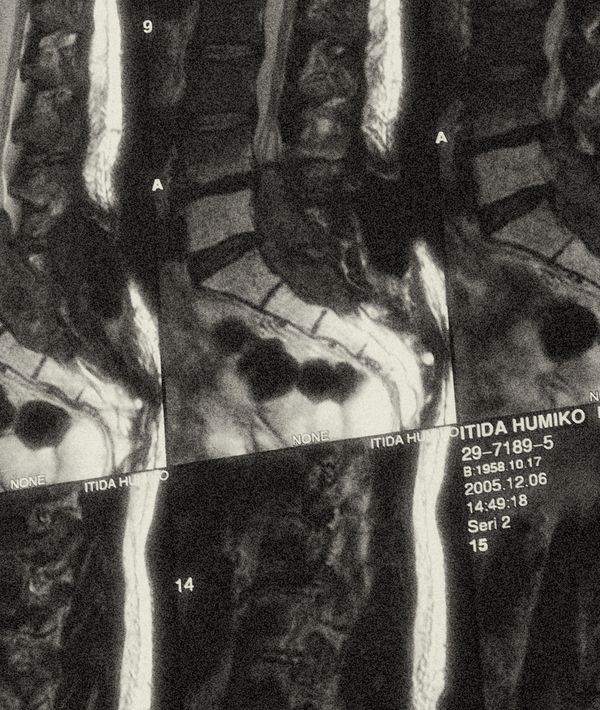

I had my camera with me in the hospital room, as I thought I might want to capture something from my last days with her. But after seeing cancer completely change her appearance, I worried that photographing her in that state would erase my earlier, healthier memories of her. I barely managed to touch my camera in those final days.